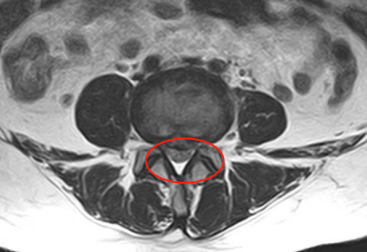

6月初,家住铜山区的李阿姨在家人的搀扶下来到必威官方首页官网betway脊柱科门诊。脊柱外科副主任医师张冶接诊后,经过仔细询问病史、查体及阅读影像学检查资料后,诊断李阿姨为腰椎间盘突出,且有明确的的手术指征,建议应用UBE技术行椎间盘切除术。

“单边双通道脊柱内镜属微创手术,优点就是创伤小、出血少、并发症少,术后恢复快,基本上第二天患者就可以下床活动了。”张冶医生介绍UBE时说,与传统开放手术相比,该手术仅需在患者后背切开两个约1cm大小的创口,然后借助人体天然解剖间隙建立微创工作通道,通过内窥镜可以清晰的显露神经根及突出椎间盘。该手术方法对椎旁肌肉损伤较小,避免伤及神经根及硬膜囊,能够较大程度地保留完整的脊柱结构,保持腰椎的稳定性和完整性。